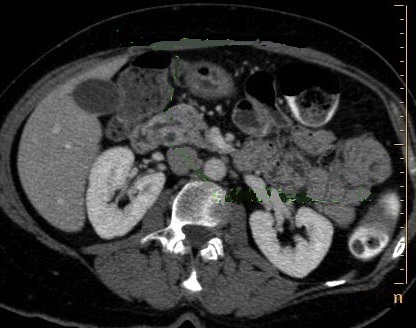

Sur les coupe TDM axilae a travers le

pancreas . Aspect de evoquer le diagnostic pancreas

divisum est le canal pancreatique dorsal croisant

par devant la voie biliaire . Les techniques CPRM et

CPRE sont des technique principale d'utilise de

choix pour diagnostic les anormalie du pancreas |